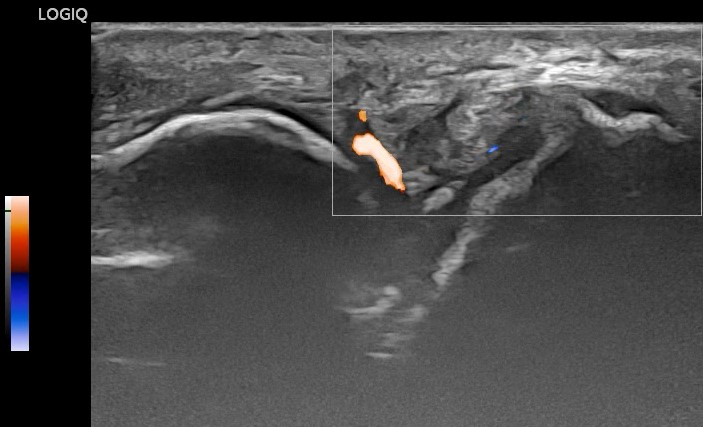

실시간 초음파 검사로인대를 스트레칭시켜서파열 정도를 확인하는 것인데요.

까만 틈을 중심으로

좌우가 벌어지는게 보이시나요?

파워도플러를 켜놓고

좀 더 빠르게 당겨봤는데요.

인대 아래 붙어있는

관절낭 캡슐까지 파열되면서

관절액이 넘어오는신호가 보입니다.

Flash artifact와 유사해서

헷갈리실 수 있는데요.

까만 틈에 국한되어

신호가 보이는 것은

관절낭 내부 액체의 빠른 이동을감지하는 것입니다.이렇듯 혈자리의 상태를초음파로 다시 확인한다면진단의 정확성을 대폭 높일 수 있습니다.